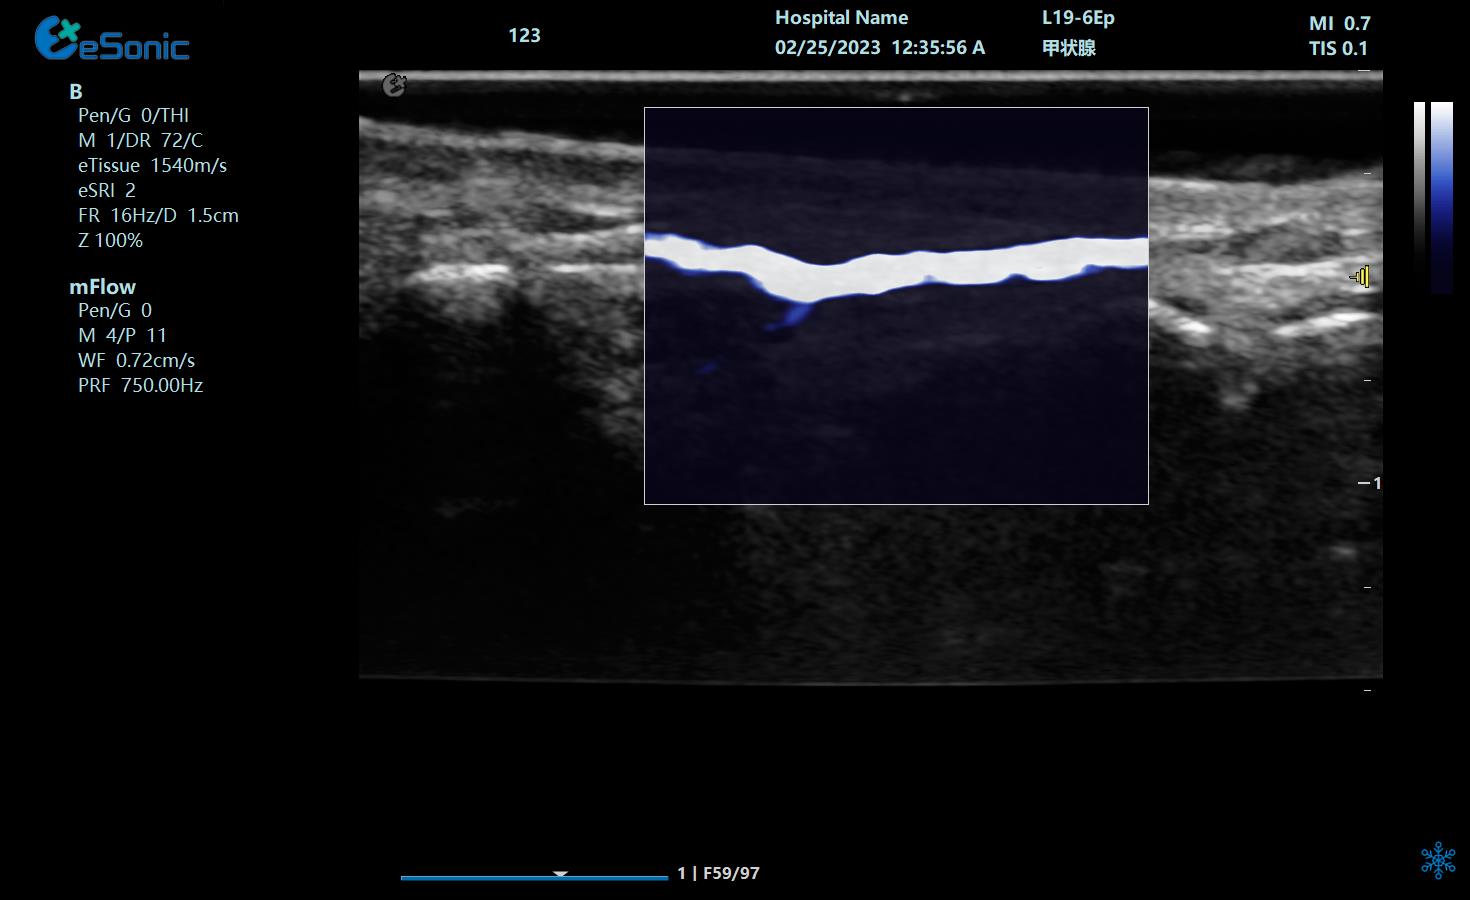

重症肺部超声

超声声像图:声束垂直胸膜线时,可见多条A线与胸膜线平行,且等间距。